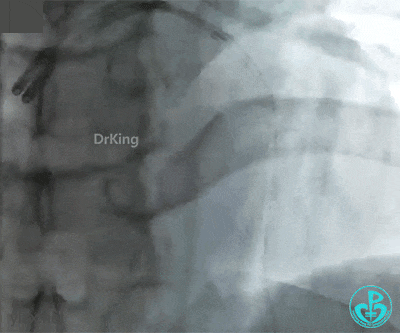

急诊冠状动脉造影

右冠脉光滑无狭窄,前降支2级血流,近端可见巨大血栓。